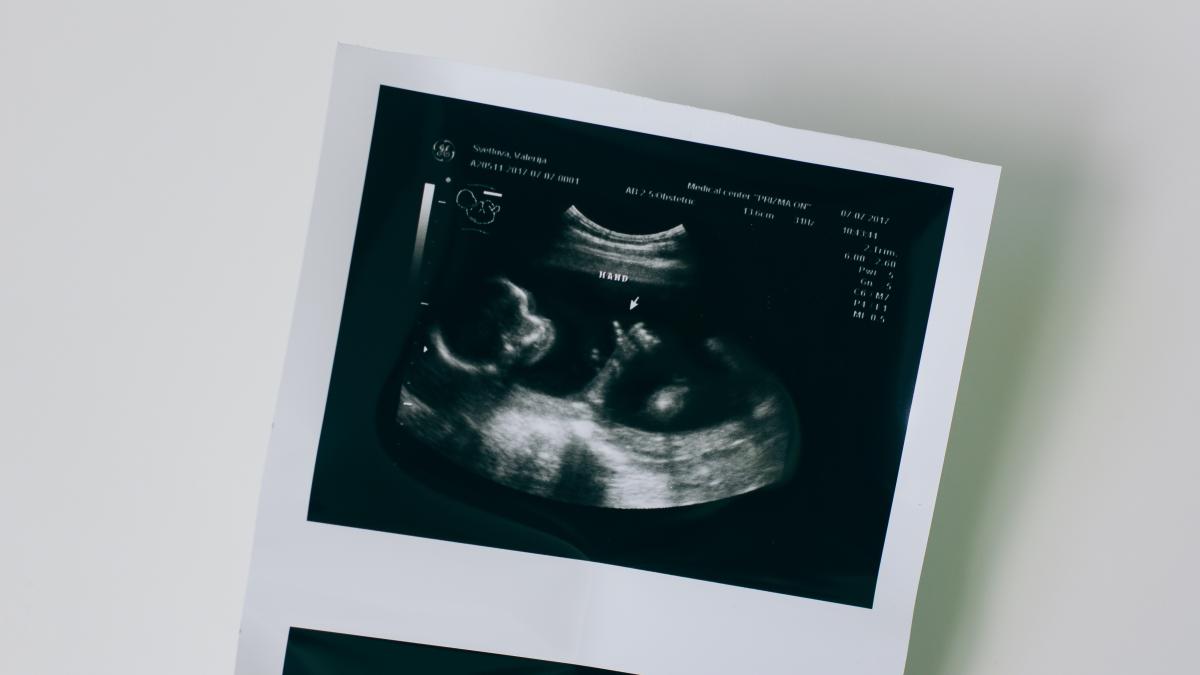

ecografie_62365300 Fotografie de la Valeriia Svietlova/ Pexels

Cercetările referitoare la făt și preferințele alimentare au arătat că bebelușii reacționează diferit la diferite mirosuri și gusturi în timp ce se află în pântec, observându-se expresiile faciale.

Experimentăm aroma printr-o combinație de gust și miros. La fetuși, acest lucru se întâmplă prin inhalarea și înghițirea lichidului amniotic în uter, scrie Ilnostrofiglio.

În uter, fătul se hrănește cu multe arome pe care le simt prin papilele gustative care se formează din a opta săptămână de sarcină. Gustul a ceea ce mănâncă mama se revarsă în lichidul amniotic iar simțul gustului progresează pe măsură ce papilele gustative se dezvoltă.

Prin urmare, fetușii reacționează la gust și miros deja în uter, dar ceea ce este curios este expresia facială a fetușilor care se modifică în funcție de preferințele alimentare.

Se pare că dulcele din mâncare dă fătului senzația de bucurie și zâmbete. Acesta este ceea ce a reieșit dintr-o cercetare efectuată de laboratorul de cercetare fetală neonatală de la Universitatea Durham și publicată în revista Psychological Science, care a surprins expresiile faciale ale fetușilor în pântece după ce mamele au mâncat două alimente foarte diferite din punct de vedere al gustului: varză și morcov.

Laboratorul de cercetare a efectuat 100 de ecografii 4D (imagini în mișcare tridimensionale) ale femeilor însărcinate (32 până la 36 de săptămâni de gestație) care au luat anterior capsule de morcovi sau de varză, iar cercetătorii au analizat reacția feților. Pentru prima dată, au fost observate reacții prenatale la gust și miros.

Conform fotografiilor 4D, fetușii au reacționat cu un zâmbet la aroma de morcov. Dulce și zaharat, a provocat o reacție de bine, iar ultrasunetele îi surprind expresia. Feții expuși gustului de varză au reacționat cu o expresie tristă de ”dezgust. (Vezi fotografiile AICI)

Cercetarea a constatat că expunerea la o cantitate mică de morcovi sau varză a fost suficientă pentru a stimula o reacție la făt. Cercetătorii cred că ceea ce mănâncă femeile însărcinate ar putea afecta preferințele gustative ale copiilor după naștere. Din acest motiv, va fi necesar un studiu de urmărire cu aceiași bebeluși după naștere pentru a vedea dacă influența aromelor pe care le-au experimentat în uter ar putea afecta modul în care oamenii acceptă diferite alimente după naștere, în special în timpul înțărcării.